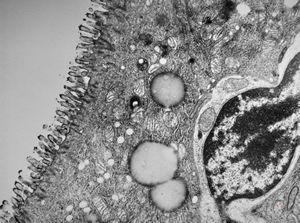

jejunum … lipid malabsorption

duodenum … lipid malabsorption